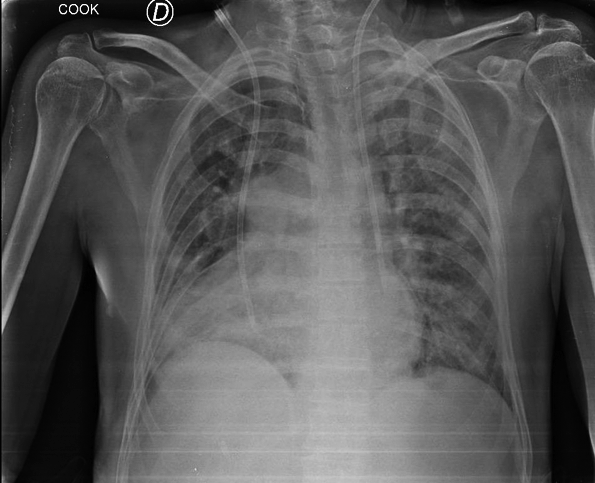

Presentamos un paciente con hiperamoniemia, que durante el estudio de la causa se diagnosticó agenesia de la vena porta, con anastomosis de la vena mesentérica a la vena renal izquierda. Ante el cuadro clínico y humoral, con compromiso neurológico, se decidió la colocación de un catéter doble lumen y se inició tratamiento mediante hemodiálisis convencional. Se colocó catéter por vía yugular izquierda presentando ubicación atípica y con mala cinética por lo que debió colocarse otro catéter doble lumen en vena subclavia derecha, ubicándose en posición convencional. La radiografía de control muestra la ubicación de ambos catéteres colocados.

Además de la anomalía vascular de la vena porta y de las cavidades cardíacas que presentes en este paciente, se detectó una anomalía vascular en las venas centrales. Se debe tener presente la posibilidad de que exista esta asociación de variantes anatómicas cuando debemos abordar vías centrales, en nuestro caso con catéter de doble lumen para tratamiento dialítico. El tip del catéter izquierdo se ubicó a nivel de seno coronario, donde el flujo sanguíneo resultó deficiente para efectuar el tratamiento dialítico. Se adjunta gráfico con esquema de las alteraciones más frecuentes de la vena cava superior doble.(1)